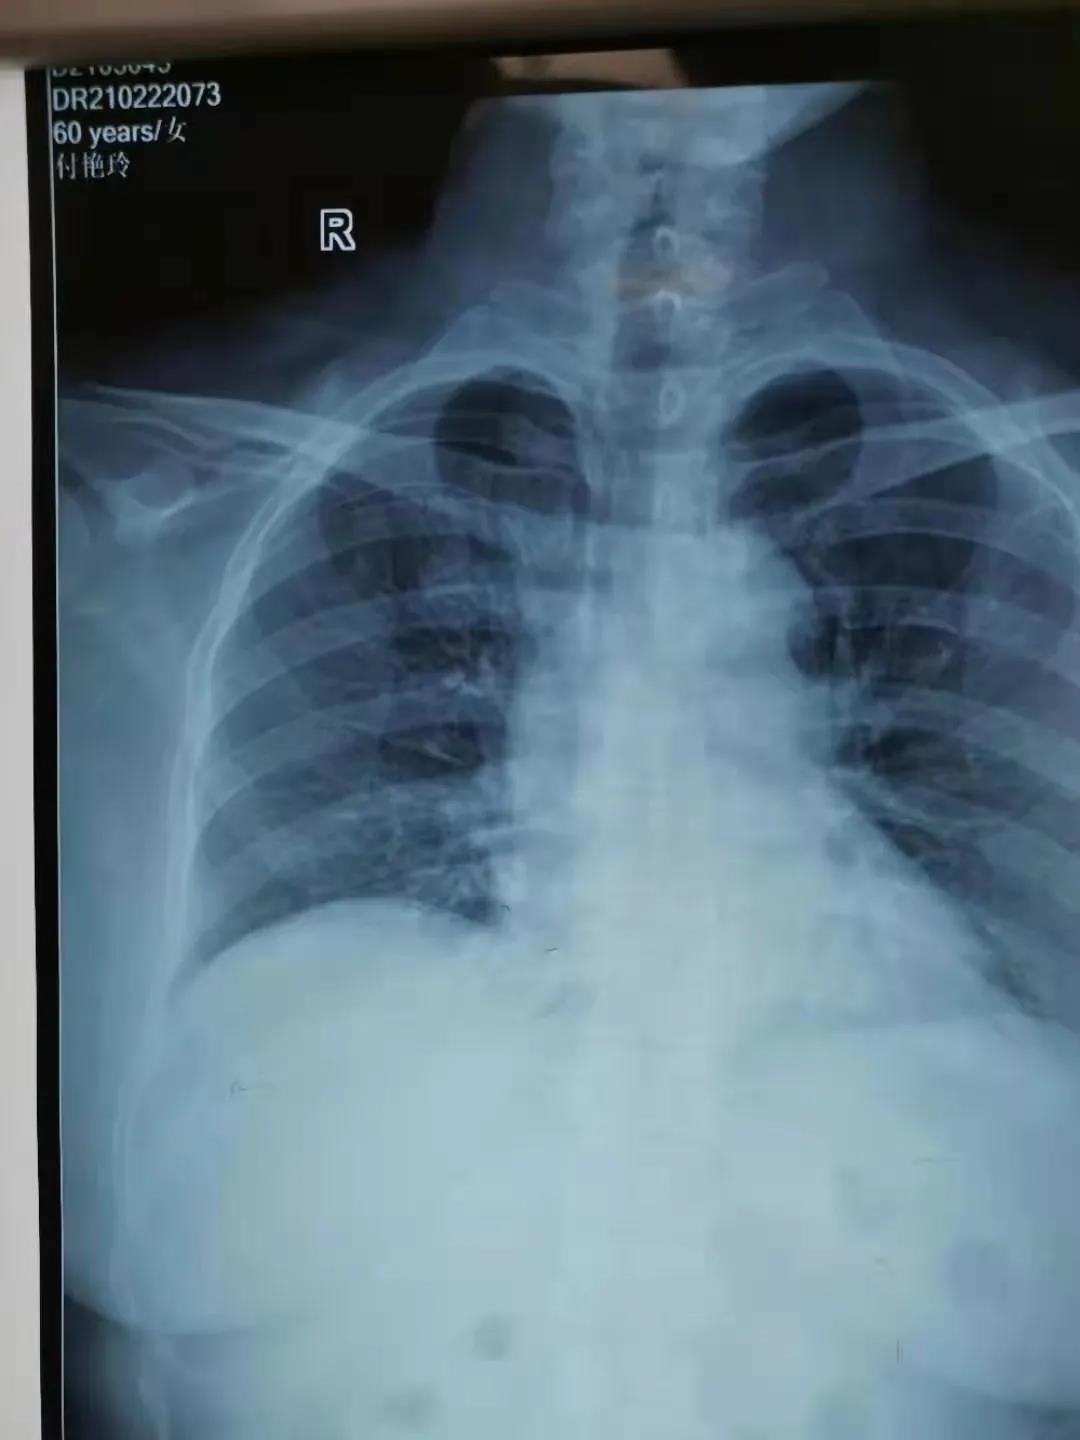

2月22日,由鄲城縣第二醫(yī)療健康服務(wù)集團(tuán)鄲城縣中醫(yī)院腫瘤血液科護(hù)士長(zhǎng)劉曉娟,護(hù)士丁星文、馬慧、張玉霞成立的靜脈治療??菩〗M,在經(jīng)過(guò)了數(shù)例PICC置管中進(jìn)行心電腔內(nèi)(ECG)定位與x線下定位結(jié)果的比較后成功運(yùn)用了ECG定位技術(shù)置管,此項(xiàng)技術(shù)的成功開(kāi)展,標(biāo)志著醫(yī)院PICC置管定位技術(shù)又上新臺(tái)階!

ECG腔內(nèi)定位技術(shù)是一種在置管過(guò)程將特殊的心電導(dǎo)聯(lián)線聯(lián)接導(dǎo)管導(dǎo)絲和心電圖機(jī),在送入導(dǎo)管過(guò)程中通過(guò)觀察心電圖上P波的特征性變化來(lái)判斷導(dǎo)管尖端的位置的方法,此項(xiàng)技術(shù)實(shí)現(xiàn)了在術(shù)中實(shí)時(shí)定位和調(diào)整導(dǎo)管頭端,達(dá)到精準(zhǔn)定位PICC導(dǎo)管頭端位置的目的。

ECG定位技術(shù)通過(guò)一“進(jìn)”兩“退”的方式(一進(jìn):當(dāng)導(dǎo)管尖端到達(dá)CAJ時(shí),可見(jiàn)高尖P波,進(jìn)入右心房后P波雙向,由高尖再轉(zhuǎn)低;一退:當(dāng)導(dǎo)管尖端從右心房退回上腔靜脈時(shí)P波恢復(fù)正常。再退:導(dǎo)管繼續(xù)后退2-3 cm到達(dá)最終正確的位置。)判斷導(dǎo)管尖端位置,及時(shí)糾正導(dǎo)管異位、極大的提高了導(dǎo)管尖端位置定位的準(zhǔn)確性,避免了因反復(fù)調(diào)整導(dǎo)管位置所致的并發(fā)癥(靜脈炎、導(dǎo)管相關(guān)感染、血栓等)及因?qū)Ч墚愇欢貜?fù)拍片,保證了患者安全,提高了工作效率。③7